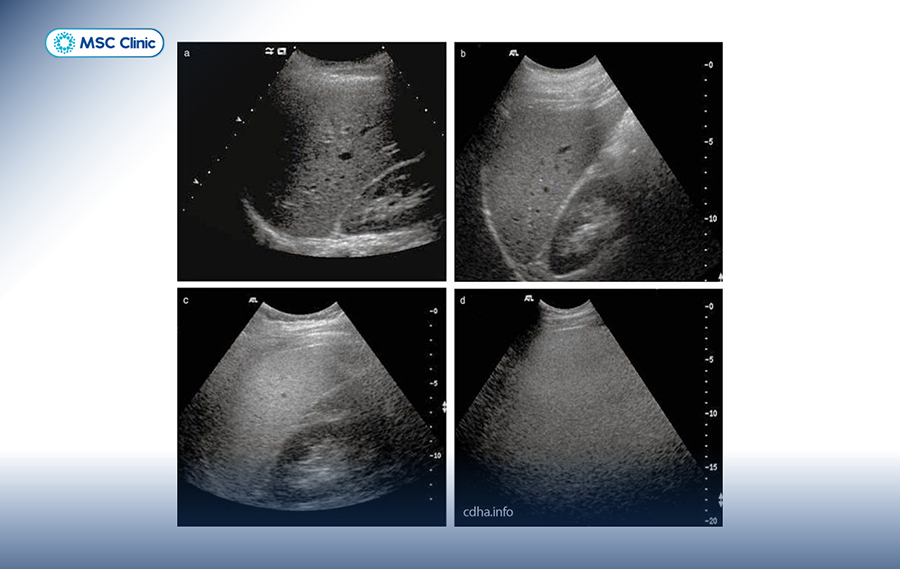

Siêu âm ổ bụng:

Đây là công cụ chẩn đoán ban đầu hiệu quả và không xâm lấn, giúp bác sĩ đánh giá trực tiếp tình trạng lá gan:

Thông thường, bệnh được phát hiện tình cờ qua siêu âm khi khám sức khỏe định kỳ. Bác sĩ sẽ kết hợp kết quả siêu âm với xét nghiệm máu và tiền sử bệnh để đưa ra chẩn đoán cuối cùng.